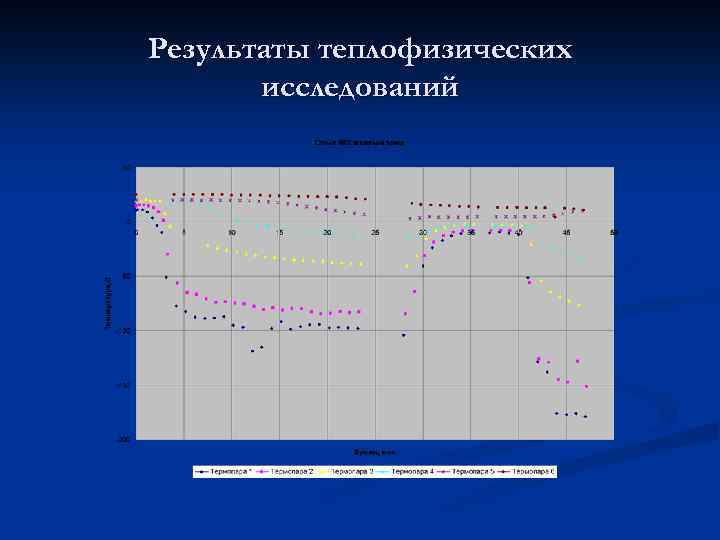

Результаты теплофизических исследований

Результаты теплофизических исследований